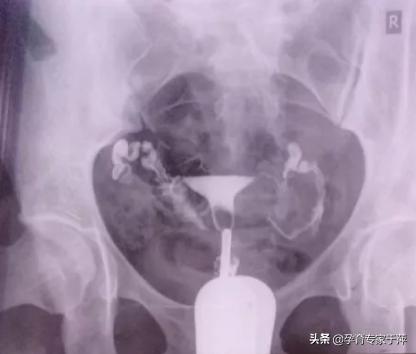

2、输卵管不通

显示一侧或双侧输卵管不显影或部分显影,盆腔没有造影剂涂抹。如果盆腔有造影剂涂抹,说明至少一侧输卵管是通的。